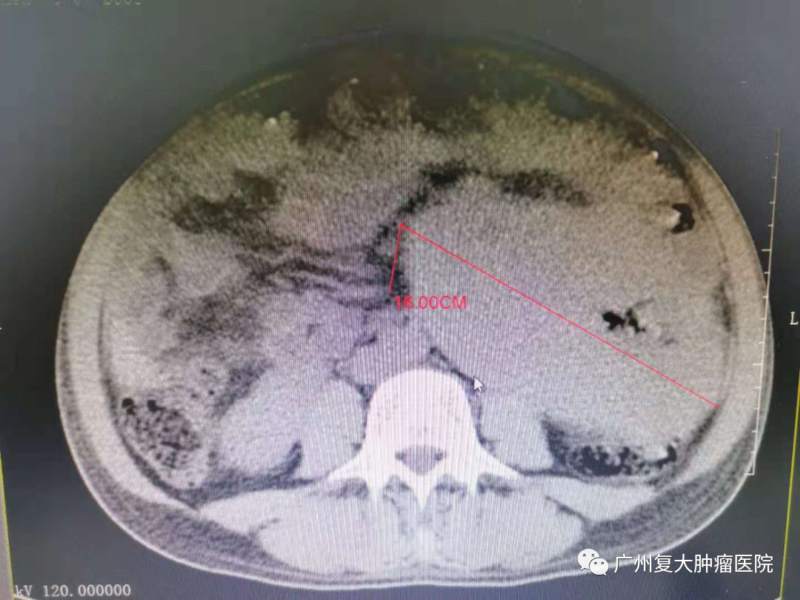

入院后,陈先生完善相关检查,CT检查显示肝右叶有巨大团块状低密度影,最大直径约22cm。这个检查结果让陈先生很错愕,“原本就只有一小块,没想到吃药打针这么久,肿瘤居然这么大了。”

肝肿瘤前后对比,肿瘤缩小,肿瘤细胞基本坏死;

肠肿瘤前后对比,肿瘤缩小,肿瘤细胞基本坏死

经过了几次介入治疗后,陈先生整个人精神了很多。值得高兴的是,他的影像资料显示肝脏与肠的肿瘤有所缩小,医生告诉他肿瘤基本坏死,降低生命的危险性。“我现在坐着躺着睡都没事,不像以前躺着肩膀痛,气还上不来出不去。”结束完此次治疗后,陈先生将回家休养,谨遵医嘱,提高自己的身体素质,他也期待下一次的复查结果。